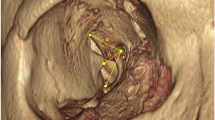

Application of the octagonal model to CT images. Firstly the orbital rim landmark is identified using a coronal view (a), for example point ‘d’ (most inferior point of lateral orbital rim). Using multiplanar reconstruction, an oblique section is drawn from here to the nearest edge of the optic canal (b). A measurement can then be taken along this plane (c) to yield depth D3